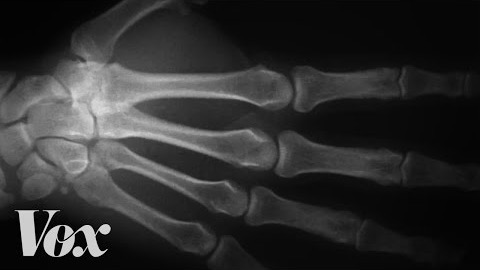

Det som händer när man knäcker med knogarna är att ledvätskan hastigt expanderar så mycket att det bildas gasbubblor i den. Det är det som är anledningen till den "knäckande" ljudet. Det knak som uppstår när man reser sig upp från att ha suttit på knä kommer snarare av att senorna glider över benknotorna.